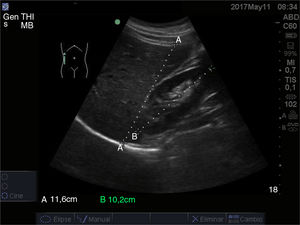

El corte oblicuo a nivel del epigastrio se usa para la visualización de la cola del páncreas y consiste en situar la sonda de manera oblicua apuntando hacia el hombro izquierdo del paciente. La cola del páncreas también se puede visualizar, en ocasiones, con cortes a nivel de flanco izquierdo utilizando el bazo como ventana acústica (fig. 11).

A la izquierda, imagen de la cola del páncreas conseguida con la sonda en disposición oblicua a nivel de epigastrio apuntando hacia el hombro izquierdo del paciente, con la arteria mesentérica superior (ams), aorta (Ao), vena cava inferior (VCI) y cuerpo vertebral (CV). A la derecha, visualización de la cola del páncreas a través de la ventana del bazo.